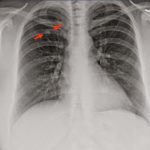

¿Son cáncer los nódulos pulmonares? Todo esto debes saber sobre ellos

Los pulmones son órganos imprescindibles para la vida humana, nos permiten respirar y oxigenan nuestro cuerpo. Las células del cuerpo necesitan oxígeno para funcionar...